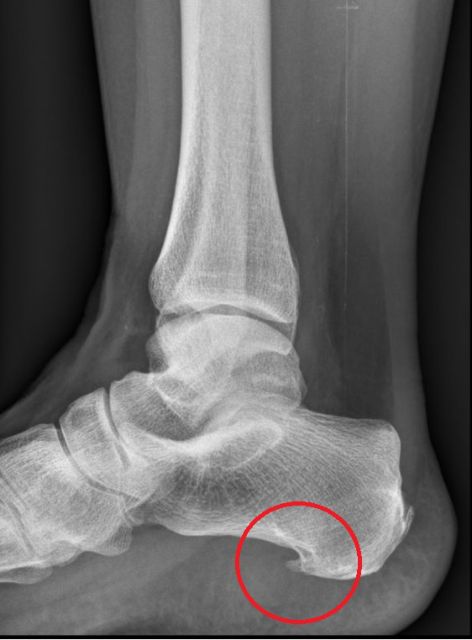

Kerbung der Plantaraponeurose bei plantarer Fasziitis (plantarer Fersensporn)

Eine häufige Erkrankung am Fuß stellt die sogenannte plantare Fasziitis (umgangssprachlich häufig als „plantarer Fersensporn" bezeichnet) dar. Dabei handelt es sich im Wesentlichen um ein degeneratives Überlastungssyndrom des Plantaraponeurosenansatzes am unteren Fersenbeinhöcker. Das klassische Leitsymptom sind plantare (an der Fußsohle) Fersenschmerzen, manchmal mit Ausstrahlung entlang der Fußsohle, und gelegentlich auch eine lokale Schwellung. Die Schmerzen entwickeln sich schleichend und sind üblicherweise belastungsabhängig. Häufig bestehen sie über viele Monate und unterschiedliche Therapieversuche von Einlagsohlen über Stoßwellenbehandlung wurden oft schon versucht.

Diese wird normalerweise kombiniert mit einer arthroskopisch kontrollierten Knochenspornabtragung am Fersenbein, um eine neuerliche Druckproblematik verhindern zu können.